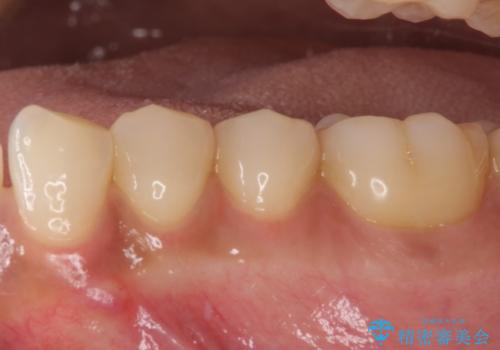

痛みでうずく 根管治療と補綴治療

- 下顎の小臼歯が食事などの度に痛みを感じるとのことで来院された患者様です。

レントゲン写真などで診査を行ったところ、左下の第一小臼歯の神経組織が壊死し、根尖部周辺の骨に炎症が認められました。

まずは根管治療を行い、症状が消退したことを確認してオールセラミッククラウンにて補綴治療を行うこととしました。

根管治療後6ヶ月でレントゲン写真を撮影したところ、根尖部周辺の炎症が消退していることが認められました。